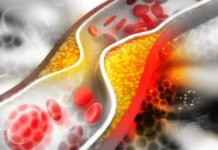

Czy jest możliwe samodzielne zapanowanie nad poziomem cholesterolu?

Co możesz zrobić dla swojego krążenia?

Warto kontrolować poziom cholesterolu, gdyż jego nadmiar może prowadzić do poważnej utraty zdrowia. Nawet w obliczu zagrożenia zawyżonym cholesterolem...